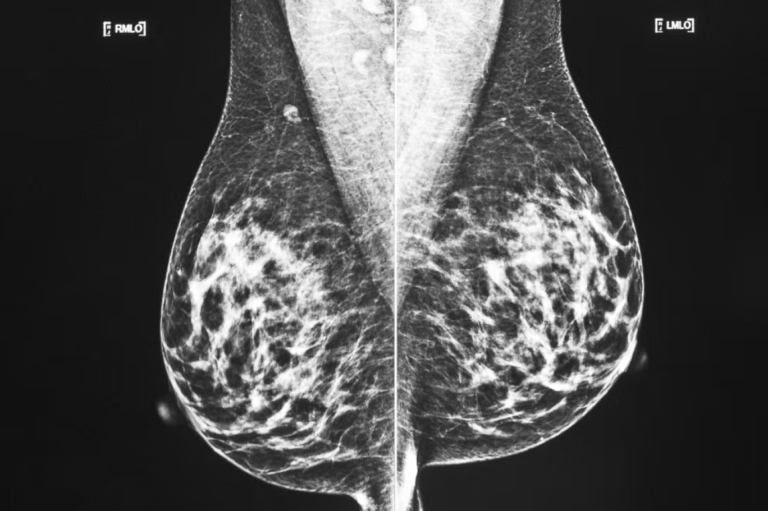

بفضل نموذج جديد من الذكاء الاصطناعي سيتمكن الأطباء من رؤية بوضوح أكبر ما إذا كان نوع عدواني من سرطان الثدي سينتشر إلى أجزاء أخرى من الجسم.

برنامج الذكاء الاصطناعي هذا طورته مجموعة من العلماء في لندن كي يكتشف أي تغيرات تطرأ في العقد الليمفاوية، المتموضعة تحت الذراع كونها واحداً من الأماكن الأولى التي ينتشر إليها سرطان الثدي لدى النساء المصابات بما يسمى “سرطان الثدي السلبي الثلاثي” triple negative breast cancer.